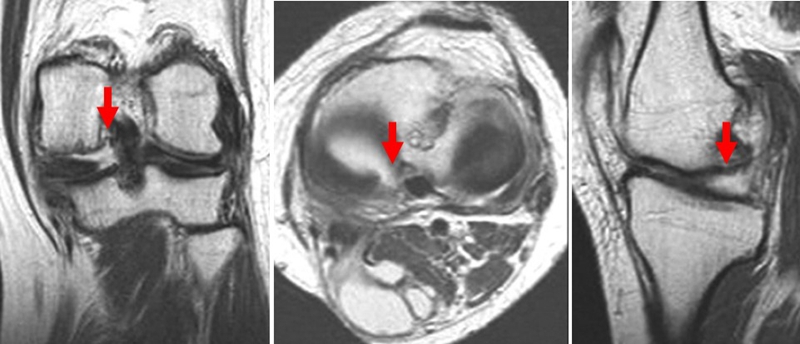

SONK与内侧半月板后根部损伤,有国外学者在SONK患者中通过MRI及关节镜检查,常可发现合并内侧半月板后根部的撕裂,该发生率可达到80%(24/30), 15例完全撕裂,9例部分撕裂。结果表明SONK可能与内侧半月板后根部撕裂后,导致股骨负重区的应力集中、软骨下骨髓水肿有关。

SONK与内侧半月板突出的相关研究中,100%(104)SONK中都有半月板突出,4个SONK在发病前因膝关节疼痛体检发现半月板突出,几个月后通过MRI检查显示存在 SONK。

研究证明半月板挤压是SONK的发病机制之一,半月板挤压的进展可能与SONK的发展有关。